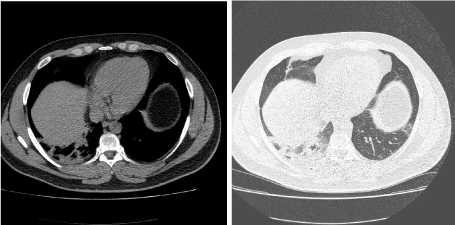

In the framework of this article we present the case of a man age 33, nonsmoker, without exposure to respiratory hazards, former professional rugby player, without a significant past medical or family history , without treatment at that time, which had presented in our medical service for hemoptysis in  small quantity, that began a month and a half before that moment , when he discharged about 50 ml of blood, the next episode of hemoptysis occurred during the day in which he presented at the hospital with a discharge of about 60 ml of blood. Whilst questioning the patient about other symptoms we found out the approximately a year ago the patient observed an increase in the volume of his right calf associated with pain, redness,  an increase of local temperature, all of which resolved spontaneously within the next few days. It is important to remark that at moment of admission the patient denied chest pain, fever, dyspnea, arthralgia, rashes, bruises or weight loss. Furthermore we must specifically mention that the patient does not have a history of chronic pulmonary disease, immunosuppressive therapy or proximity to known tuberculosis patients. The physical examination at the time of the hospitalization did not reveal any notable elements. The complete blood count and biochemistry tests showed a biological inflammatory syndrome without leukocytosis; it is worth mentioning that multiple tests of the D-dimers were negative.  A first tomographic examination showed a pulmonary consolidation process in the right inferior lobe with air bronchogram sign and minimal bilateral pleural fluid accumulation (Figure 1). A second tomographic examination, preformed 7 days later, revealed bilateral pulmonary consolidation with the same characteristics as the previous observed consolidation (Figure 2). Through serial bronchoscopic examinations, an evolution of the lesions was observed, at the first examination we observed rare bilateral anthracotic spots and an active hemorrhagic source at the level of the right basal pyramid (the precise source of the bleeding was not identified, just that the source could be a intersegmentary carina and consequently the hypothesis of broncho-vascular fistula arouse), no other notable elements were identified. The latter bronchoscopic examination recorded the cessation of the bleeding (under the hemostatic effect of the medication), and without the constant stream of blood we identified an area of vascular ectasic hyperplasia at the right anterobazal carina. A hematology consult revealed a hereditary thrombophilia thru a mutation of the MTHFR gene - methyl tetrahididrofolat reductase (C677 mutation T A1298C- heterozygous genotype) and the mutation of the second coagulation factor - prothrombin  - heterozygous genotype.

Figure 1. A first tomographic examination showed a pulmonary consolidation process in the right inferior lobe with air bronchogram sign and minimal bilateral pleural fluid accumulation